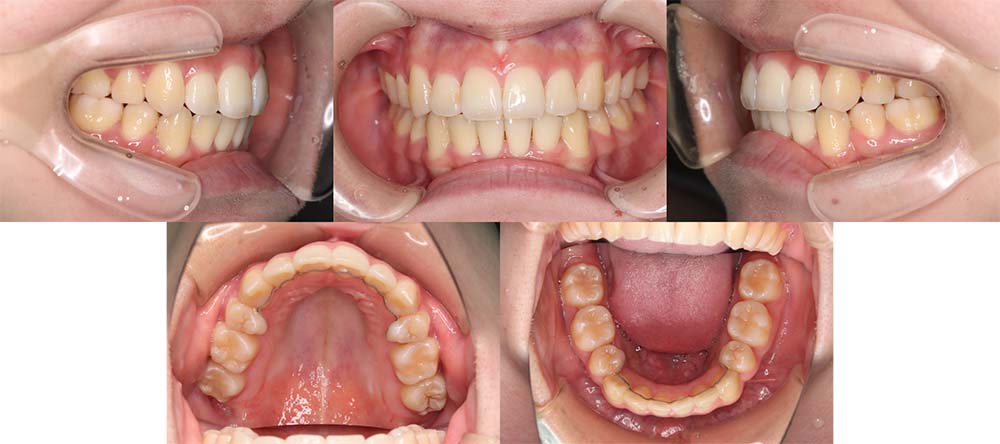

| 症例分類 | 上下顎前突、口唇突出 |

| 診断名 | 口唇突出を伴う上下軽度叢生 |

| 主訴 | 前歯が気になる |

| 年齢 | 15歳8ヶ月 |

| 性別 | 女性 |

| 抜歯部位 | 上下左右の第一小臼歯(4本) |

| 使用装置 | 表側のワイヤー装置 |

| 治療期間 | 1年9ヶ月 |

| 保定装置 | 固定式保定装置、取り外し式保定装置(8時間) |

| 費用 | [検査・診断料] ¥49,500 [基本施術料] ¥792,000 [調整料] ¥4,400/回 [抜歯] ¥5,500/本 [保定装置] ¥55,000(税込) 抜歯や虫歯治療は他院にて費用が別途かかります。(抜歯¥4,000〜10,000/本)

当初は前歯のガタガタを気にされており、上顎の部分治療を希望されました。しかしながら、上顎前歯の叢生のみの改善は可能だが、口唇突出感はなくなり、口が自然に閉じるようにするためには抜歯が必要なことを説明したところ、抜歯して治療することを希望されました。

上下第一小臼歯を抜去して表側のマルチブラケット装置で治療しました。顎間ゴムの協力度が良く予定より早く治療が終了することができました。

口唇突出感をなくし、しっかりと咬合することができました。